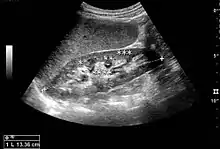

Figure 5. Simple renal cyst with posterior enhancement in an adult kidney. Measurement of kidney length on the US image is illustrated by '+' and a dashed line.[1]